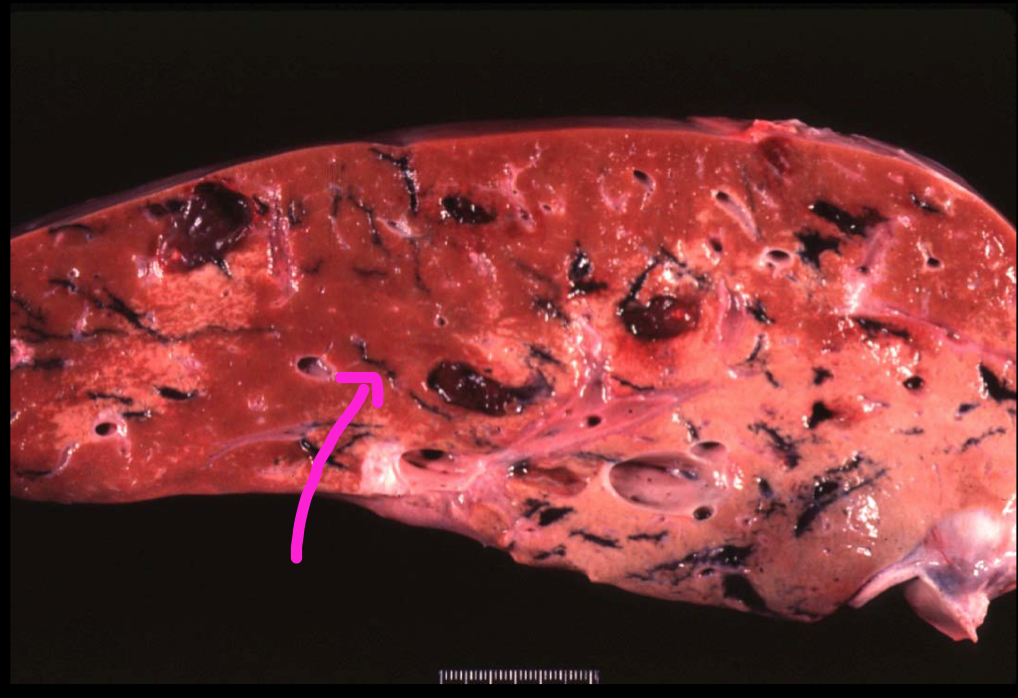

Fasciola magna

pigmented tracts*